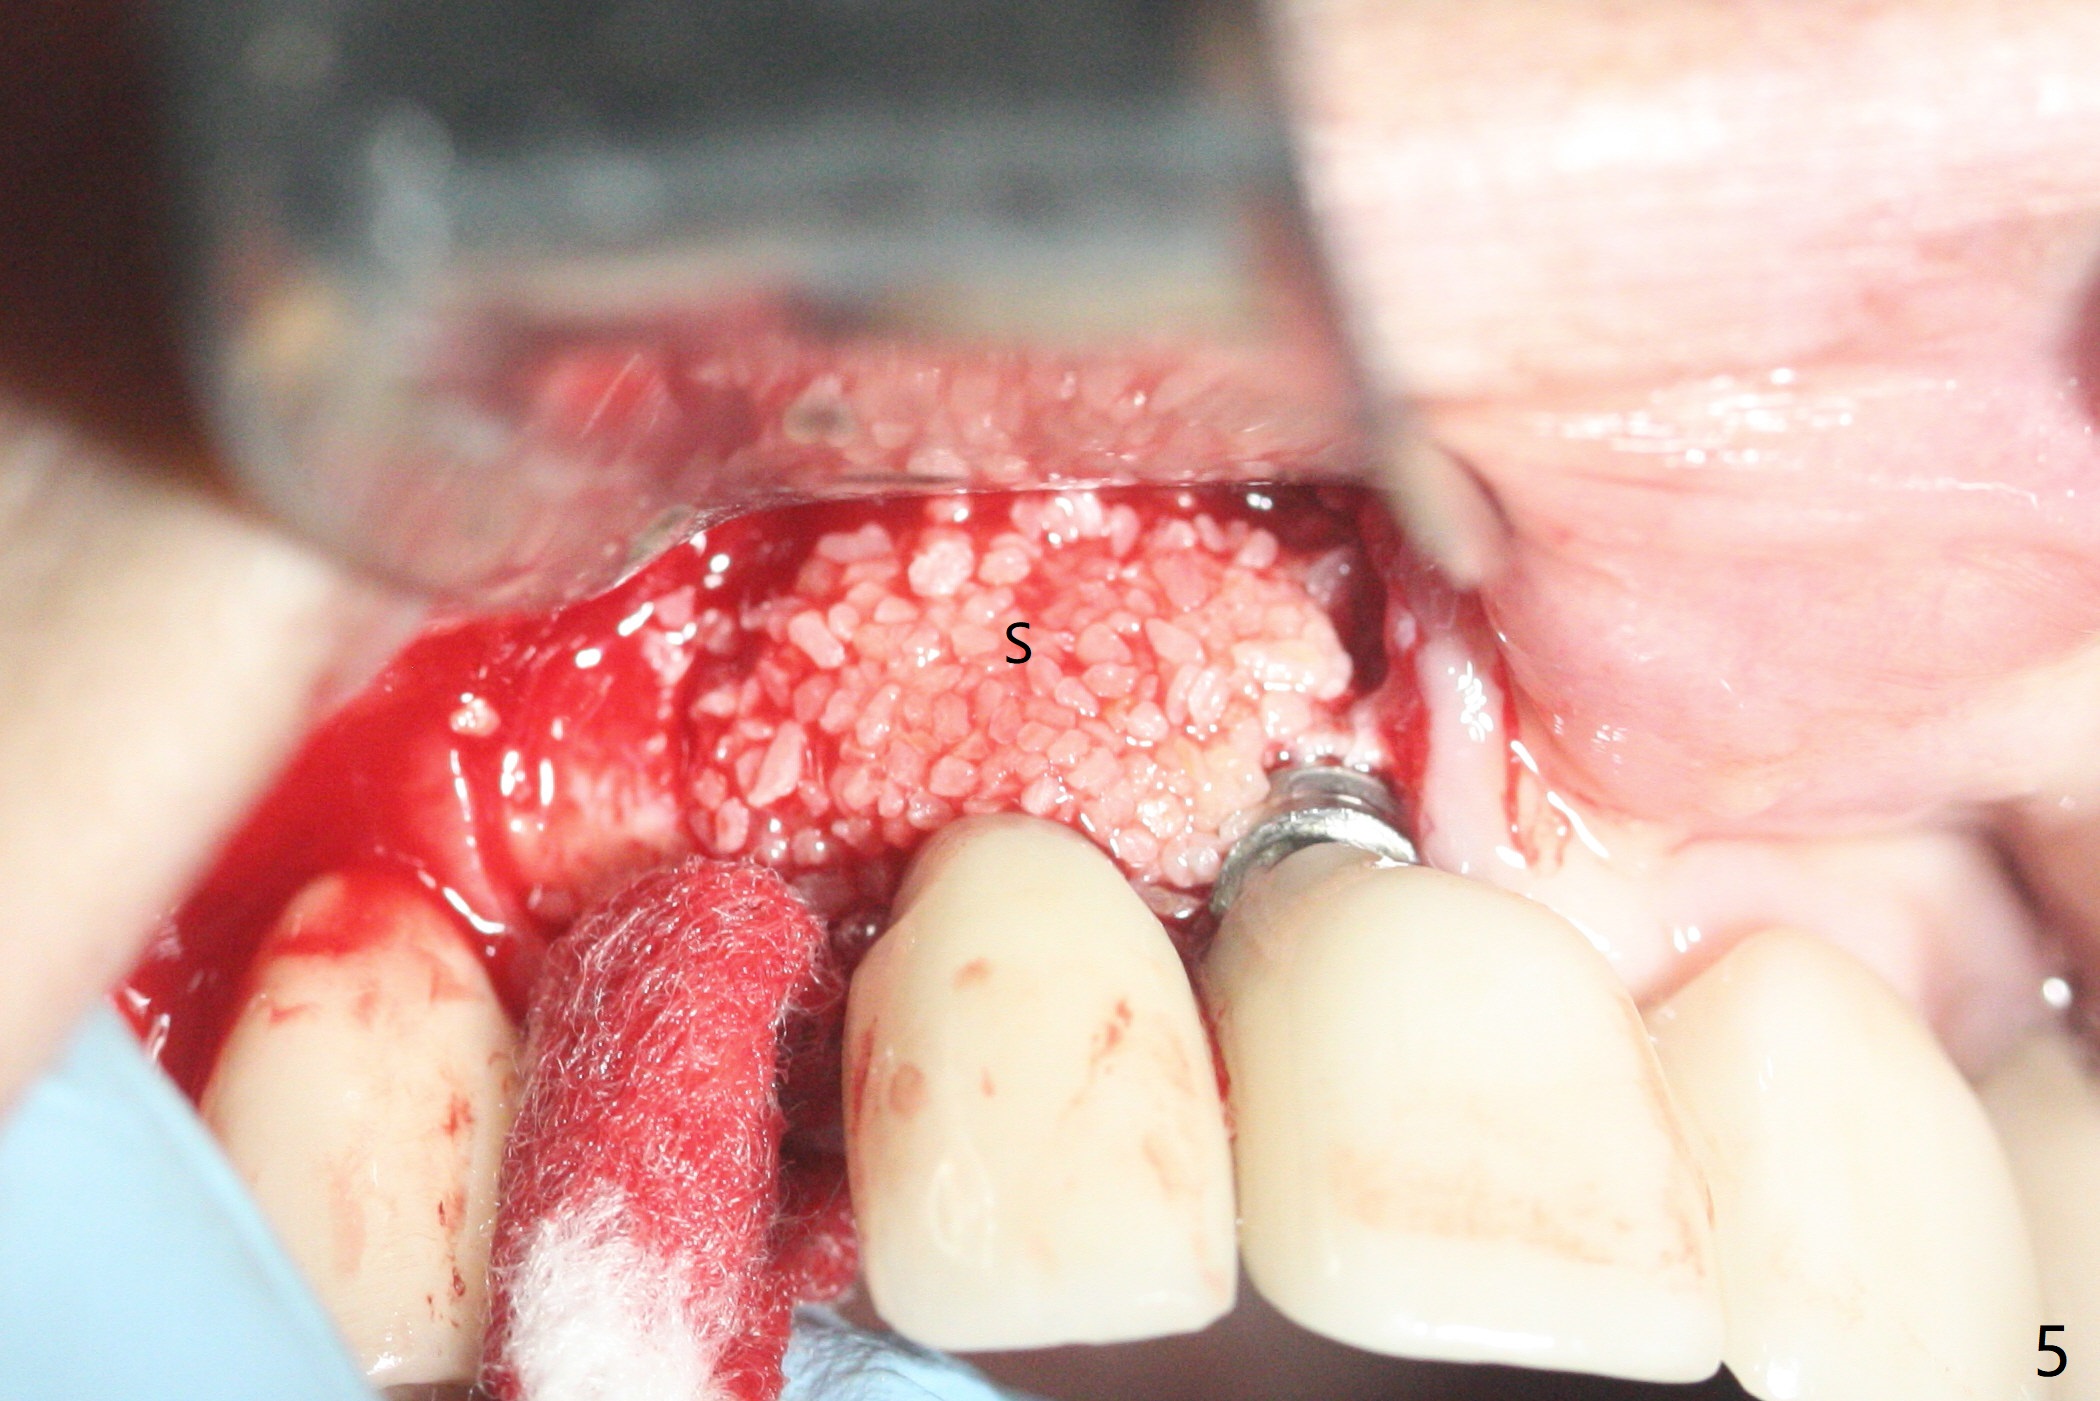

64岁女3-7牙桥,7号牙植体颊侧牙龈缘红肿(图一:*),脓液(图二:^),需要切开清洗,但是6号牙桥墩颊侧非角化龈(N)妨碍切口,所以必须去除桥墩,暴露牙槽嵴顶角化龈(图三:K),容易切开,最后缝合而不容易出血,伤口容易愈合。切开清创后重大发现是牙冠边缘(图四:^)直接接触植体微螺纹,没有基台与牙龈之间形成的屏障,有利于口腔细菌直接感染植体。直感告诉术者必须缩短牙冠边缘,抛光。然后缺损处放置粘性骨粉(图五,八:S,与图七(术前)比较),表面覆盖PRF膜,缝合(图六)。准备术后尽早去除牙冠,预防细菌再次感染。并且在6号牙位植入2x8.5毫米植体。